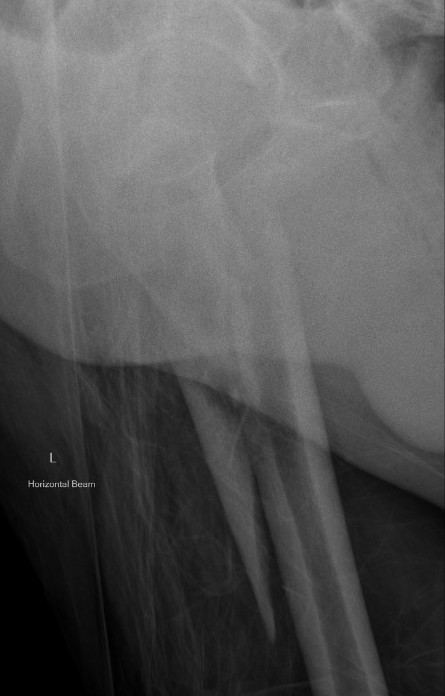

3. Varus malreduction associated with non union

- anatomical reduction key to union

- case series of 102 subtrochanteric fractures treated with IMN

- all nonunion occurred with varus > 10 degrees

Position

Lateral

- helps reduction of distal fragment to flexed proximal fragment

- easier piriformis access

Supine on traction table

- easier imaging

- longitudinal traction

Entry point

Greater trochanteric

- simple

- need proximal fragment reduced

Piriformis

- may aid reduction, as a trochanteric nail will push proximal fragment into valgus

- more difficult to obtain